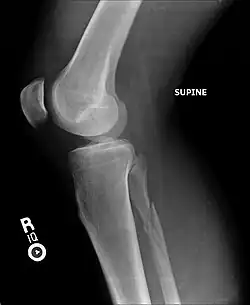

Ankle radiographs are used to detect widening of the tibiofibular syndesmosis or medial clear space. The medial clear space is the area between the talus of the ankle and the medial malleolus. Damage to the deltoid ligament and syndesmotic ligaments result in mortise instability, causing the talus to laterally shift and widen the medial clear space.[4][12] A clinical study, conducted in 2006 and published in the Journal of Bone and Joint Surgery, found that the medial clear space size of a normal ankle and an injured ankle measured at 4 millimetres and 5.4 millimetres in length respectively.[11] To confirm diagnosis, full-leg radiographs are used to inspect for fractures of the proximal fibula and widening of the interosseous clear space (or tibiofibular clear space). The interosseous clear space is the area between the medial side of the fibula and lateral side of the tibia. A peer-reviewed study, published in Injury in 2004, found that an interosseous clear space greater than 10 millimetres indicates diastasis of the syndesmotic ligaments.[4]

If necessary, computed tomography (CT) or magnetic resonance imaging (MRI) may also be used to clarify diagnosis. MRI scans can check for interosseous membrane or tibial tubercle damage if high instability of the ankle is diagnosed.[8][11] Arthroscopy may be used to diagnose a syndesmotic lesion but is often not recommended due to operative difficulty.[13] Stress radiographs of the ankle are used to assess the integrity of the deltoid ligament and tibiofibular syndesmosis.[9][13] The size of the medial clear space can also be measured using stress radiography.[11]